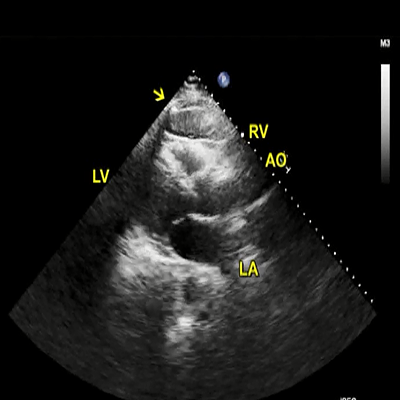

This is an adult patient who underwent left ventricular assist device (LVAD) placement for dilated cardiomyopathy and heart failure.